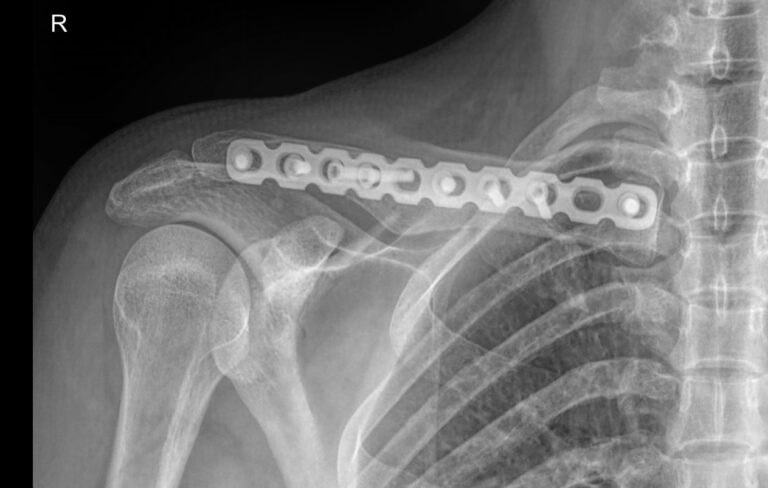

Ключица вместе с лопаткой составляет пояс верхней конечности и участвует в присоединении руки к грудной клетке. Ключица тонкая и хрупкая, но благодаря своей изогнутой форме отлично справляется со своей функцией. Перелом может произойти при сильном прямом ударе или падении. Во многих случаях перелому сопутствует вывих в акромиально-ключичном суставе. Реже наблюдаются дистрофические поражения сустава или онкология. Факторами риска выступают эндокринные нарушения, прием гормональных препаратов в лечебных и спортивных целях, а также возраст.

Рентгенография используется в качестве первичного  исследования при любых патологиях ключицы. Классическая рентгеновская съемка неинвазивная, безболезненная и простая в выполнении для пациента. Обычно такого исследования достаточно для подтверждения диагноза или отслеживания лечебного процесса. Что касается ионизирующего излучения, дозы, излучаемые  современными аппаратами настолько малы, что не набирают и минимально допустимых показателей даже при выполнении серии снимков.

Что покажет рентген ключицы

• Состояние мягких тканей;

• Наличие перелома, в том числе заживающего или уже зажившего, его местоположение;

• Наличие вывиха;

• Состояние суставной щели акромиально-ключичного сустава и грудино-ключичного сочленения;

• Изменения в костной ткани ключицы.